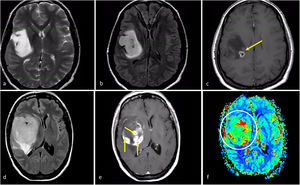

Características de imagen en dos pacientes con astrocitoma IDH-mutado grado 4. a-c) Paciente de 37 años. Axial T2w, FLAIR y T1w poscontraste. Extensa lesión bien definida hiperintensa en T2w (a) con la correspondiente hipointensidad en FLAIR y delgado borde hiperintenso periférico en (b), consistente con el signo de mismatch T2/FLAIR que sugiere mutación en IDH. Se observa un pequño foco de realce y necrosis dentro del margen profundo del tumor (c), lo que sugiere un grado 4. Obsérvese también que, en este caso, una biopsia que no captara la necrosis podría subestimar el grado del tumor y considerarlo de grado 2-3. La detección de características de imagen de grado 4 dentro de un tumor con mismatch T2/FLAIR parece ser una manifestación específica de astrocitoma IDH-mutado grado 4. d-f) Paciente de 49 años. FLAIR axial (d), T1w poscontraste (e), y mapa de color de CBV derivado de DSC-PWI (f). Masa tumoral bien definida y redondeada en FLAIR (d) con áreas internas de realce sólido (e) dentro del tumor no captante. Pequeños focos de necrosis (flechas en e) y CBV claramente elevado (círculo en f). Cabe destacar que existía una necrosis más extensa en otras partes del tumor que no aparecen en esta figura. Un glioma con aspecto de grado 4 en un paciente menor de 55 años con algunas características atípicas para un glioblastoma, como una morfología redondeada clara y márgenes bien definidos, podría sugerir un astrocitoma IDH-mutado grado 4

CBV: volumen sanguíneo cerebral; DSC-PWI: imagen de perfusión dinámica; IDH: gen isocitrato deshidrogenasa.

Astrocitoma IDH-mutado grado 4Este subgrupo de astrocitomas con mutación de IDH ha sido menos estudiado en comparación con los grados 2-3, por lo que sigue suponiendo un gran desafío radiológico. Lamentablemente, estos tumores a menudo se agrupan (y, en consecuencia, están infrarrepresentados) con los de grados 2-3 dentro de la categoría más amplia de astrocitomas IDH-mutados. Sin embargo, esta agrupación generalizada puede ser contraproducente porque: 1) las diferencias entre los tumores IDH-mutados grados 2-3 y 4 son vitales para el manejo de los pacientes; y 2) la aplicación de estos indicadores de imagen en los grados 2-3 y 4 puede no arrojar resultados precisos para este último, que comparte características de imagen con los glioblastomas (del mismo grado histológico). De hecho, según las hipótesis, las imágenes de los astrocitomas IDH-mutados grado 4 se encuentran entre las de aquellos de grado 2-3 (con los que comparten la mutación IDH) y la de los glioblastomas sin mutaciones IDH (con los que comparten el grado histológico). Por lo tanto, según el grado histológico, este tumor debería presentar necrosis, restricción de la difusión y CBV elevado con frecuencia; no obstante, debido a la presencia de mutacion IDH debería manifestarse en pacientes menores de 55 años, estar bien definido y con una morfología nodular/ovalada. Además, recientemente se ha descrito la presencia de mismatch T2-FLAIR como específico también para el astrocitoma IDH-mutado grado 4. Si sumamos esto a los conocimientos previos, cabe pensar que un tumor con un mismatch T2/FLAIR que presenta focos de necrosis, realce prominente, restricción de la difusión o CBV elevado debería ser muy probablemente un astrocitoma IDH-mutado grado 465,66 (fig. 7).